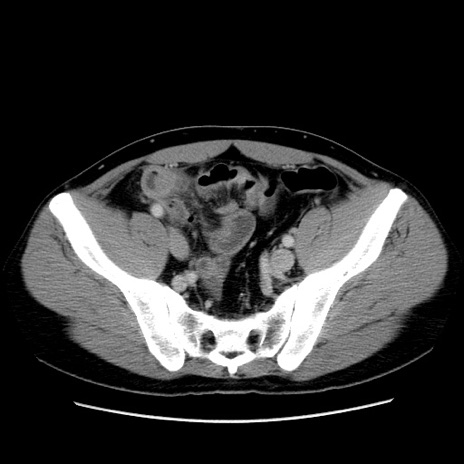

症例4(横断像)

【症例】30歳代男性

【主訴】腹痛、嘔吐

【現病歴】昨晩から突然の腹痛あり、その後嘔吐、軟便も出現。腹痛が改善しないため救急搬送となる。2日前にしめ鯖の食事歴あり。

【身体所見】意識清明、苦悶様、BP 135/90mmHg、BT 35.7℃、腹部:平坦、やや硬、心窩部〜臍部に自発痛、圧痛あり、筋性防御+、反跳痛-

【データ】WBC 8100、CRP 0.57